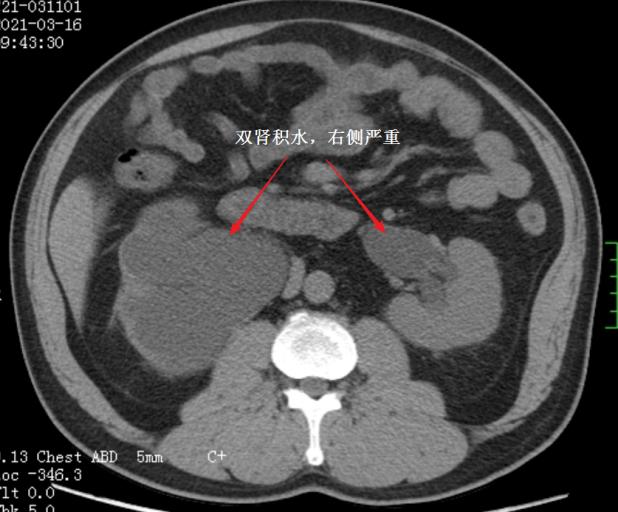

CT发现双肾积水

近期,我院马王堆院区泌尿四科收治一位来自山西的大哥,因为尿频尿急困扰多年,在山西省多家就诊,发现这位病人患有罕见的“盆腔脂肪增多症”,合并有“腺性膀胱炎”、“双侧输尿管下端狭窄梗阻并双肾重度积水”,治疗2年,双肾积水仍然没有缓解(图1)。自己在百度上查找相关知识,惊喜的发现网上有泌尿四科报道一篇与自己病情十分相似的科普文章,电话联系后打“飞的”来到湖南省人民医院泌尿四科。

泌尿四科专家团队分析,与科普报道的盆腔脂肪增多症的病人相比,虽然盆腔在CT上也呈现出倒梨形,但这位病人的盆腔周围脂肪相对少,膀胱容量及功能基本正常,膀胱镜下腺性膀胱炎轻微,然而输尿管扭曲及肾脏积水程度却更为严重。经过充分讨论后,为病人精细制定个性化的治疗方案,行腹腔镜下双侧输尿管松解+输尿管膀胱再植+双侧输尿管支架置入。术后复查CT,双肾积水明显好转,患者住院11天后快速康复出院。